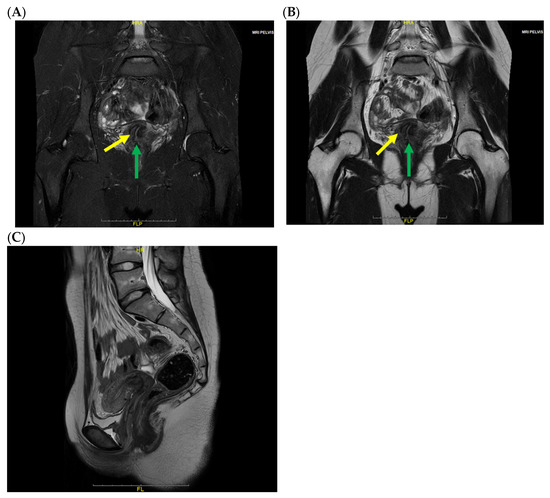

Background: Vulvovaginitis is a common condition in pediatric and adolescent female patients and is most frequently caused by infection. Although non-infectious etiologies are less common, they should be considered, particularly in cases that are refractory to standard treatment. Case: We report a rare case of a 16-year-old adolescent who was ultimately diagnosed with obstructed hemivagina and ipsilateral renal anomalies (OHVIRA) syndrome after experiencing recurrent vulvovaginitis for more than one year. Despite repeated antimicrobial treatments, her symptoms persisted. Further imaging studies revealed uterine didelphys with an obstructed hemivagina and ipsilateral renal agenesis. Surgical resection of the vaginal septum resulted in complete resolution of symptoms. Conclusions: Müllerian anomalies, such as OHVIRA syndrome, should be considered in the differential diagnosis for adolescents with recurrent vulvovaginitis refractory to conventional therapy. Delayed diagnosis may result in complications that significantly impair both quality of life and future reproductive potential. Full article

Figure 1